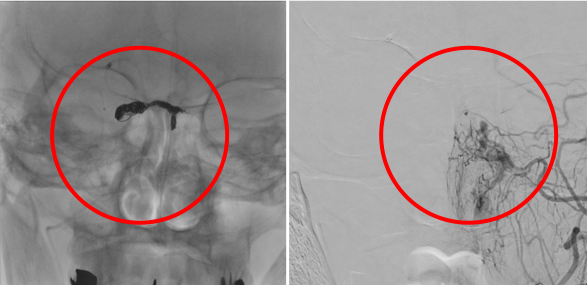

前交通動脈瘤

術前の造影写真です。〇内に脳動脈瘤が造影されています。

動脈瘤内にマイクロカテーテルを挿入しステントを展開しています。

術後の造影写真です。主幹動脈は温存できており、動脈瘤は造影されなくなっています。